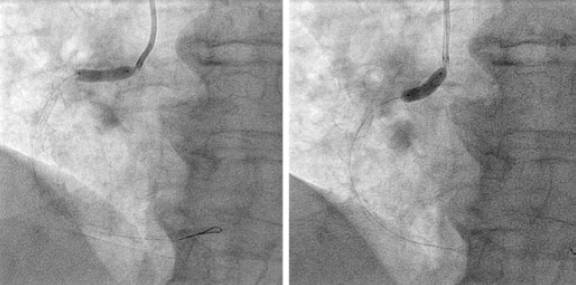

Afterwards we proceeded with the eventless advancement of a new zotarolimus-coated stent (Medtronic Resolute Onyx, 4 × 22 mm) towards the proximal segment by navigating inside the guiding catheter extension device (figure 3). This second stent was implanted and anchored to the previous one and adjusted to the ostium. It was dilated with high pressure with the delivery balloon including the visible segment protruding into the aorta in order to achieve the longitudinal shortening of the stent by overexpansion (figure 4).

Figure 4. Post-dilatation with balloon of the previous implanted stents especially of the portion protruding into the aorta in order to achieve the greatest possible longitudinal shortening.